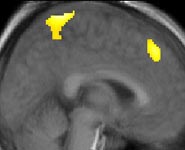

Learning from competitors is a critically important form of learning for animals and humans. A new study has used brain imaging to reveal how people and animals learn from failure and success. The team from Bristol University led by Dr Paul Howard-Jones , Senior Lecturer in Education in the Graduate School of Education and Dr Rafal Bogacz , Senior Lecturer in the Department of Computer Science , scanned the brains of players as they battled against an artificial opponent in a computer game. In the game, each player took turns with the computer to select one of four boxes whose payouts were simulating the ebb and flow of natural food sources. Players were able to learn from their own successful selections but those of their competitor failed completely to increase their neural activity. Instead, it was their competitor's unexpected failures that generated this additional brain activity. Such failures generated both reward signals in the brains of the players, and learning signals in regions involved with inhibiting response.